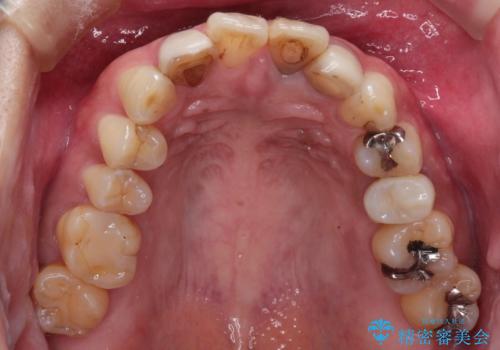

- 全体的なガタガタと前歯をきれいにしたいとのことで来院されました。

下の歯は重度のガタガタがあり、上の前歯は何本かが神経の治療がしてある状態でした。

インビザラインにて歯並びを整え、上顎の前歯にセラミックを装着する計画としました。